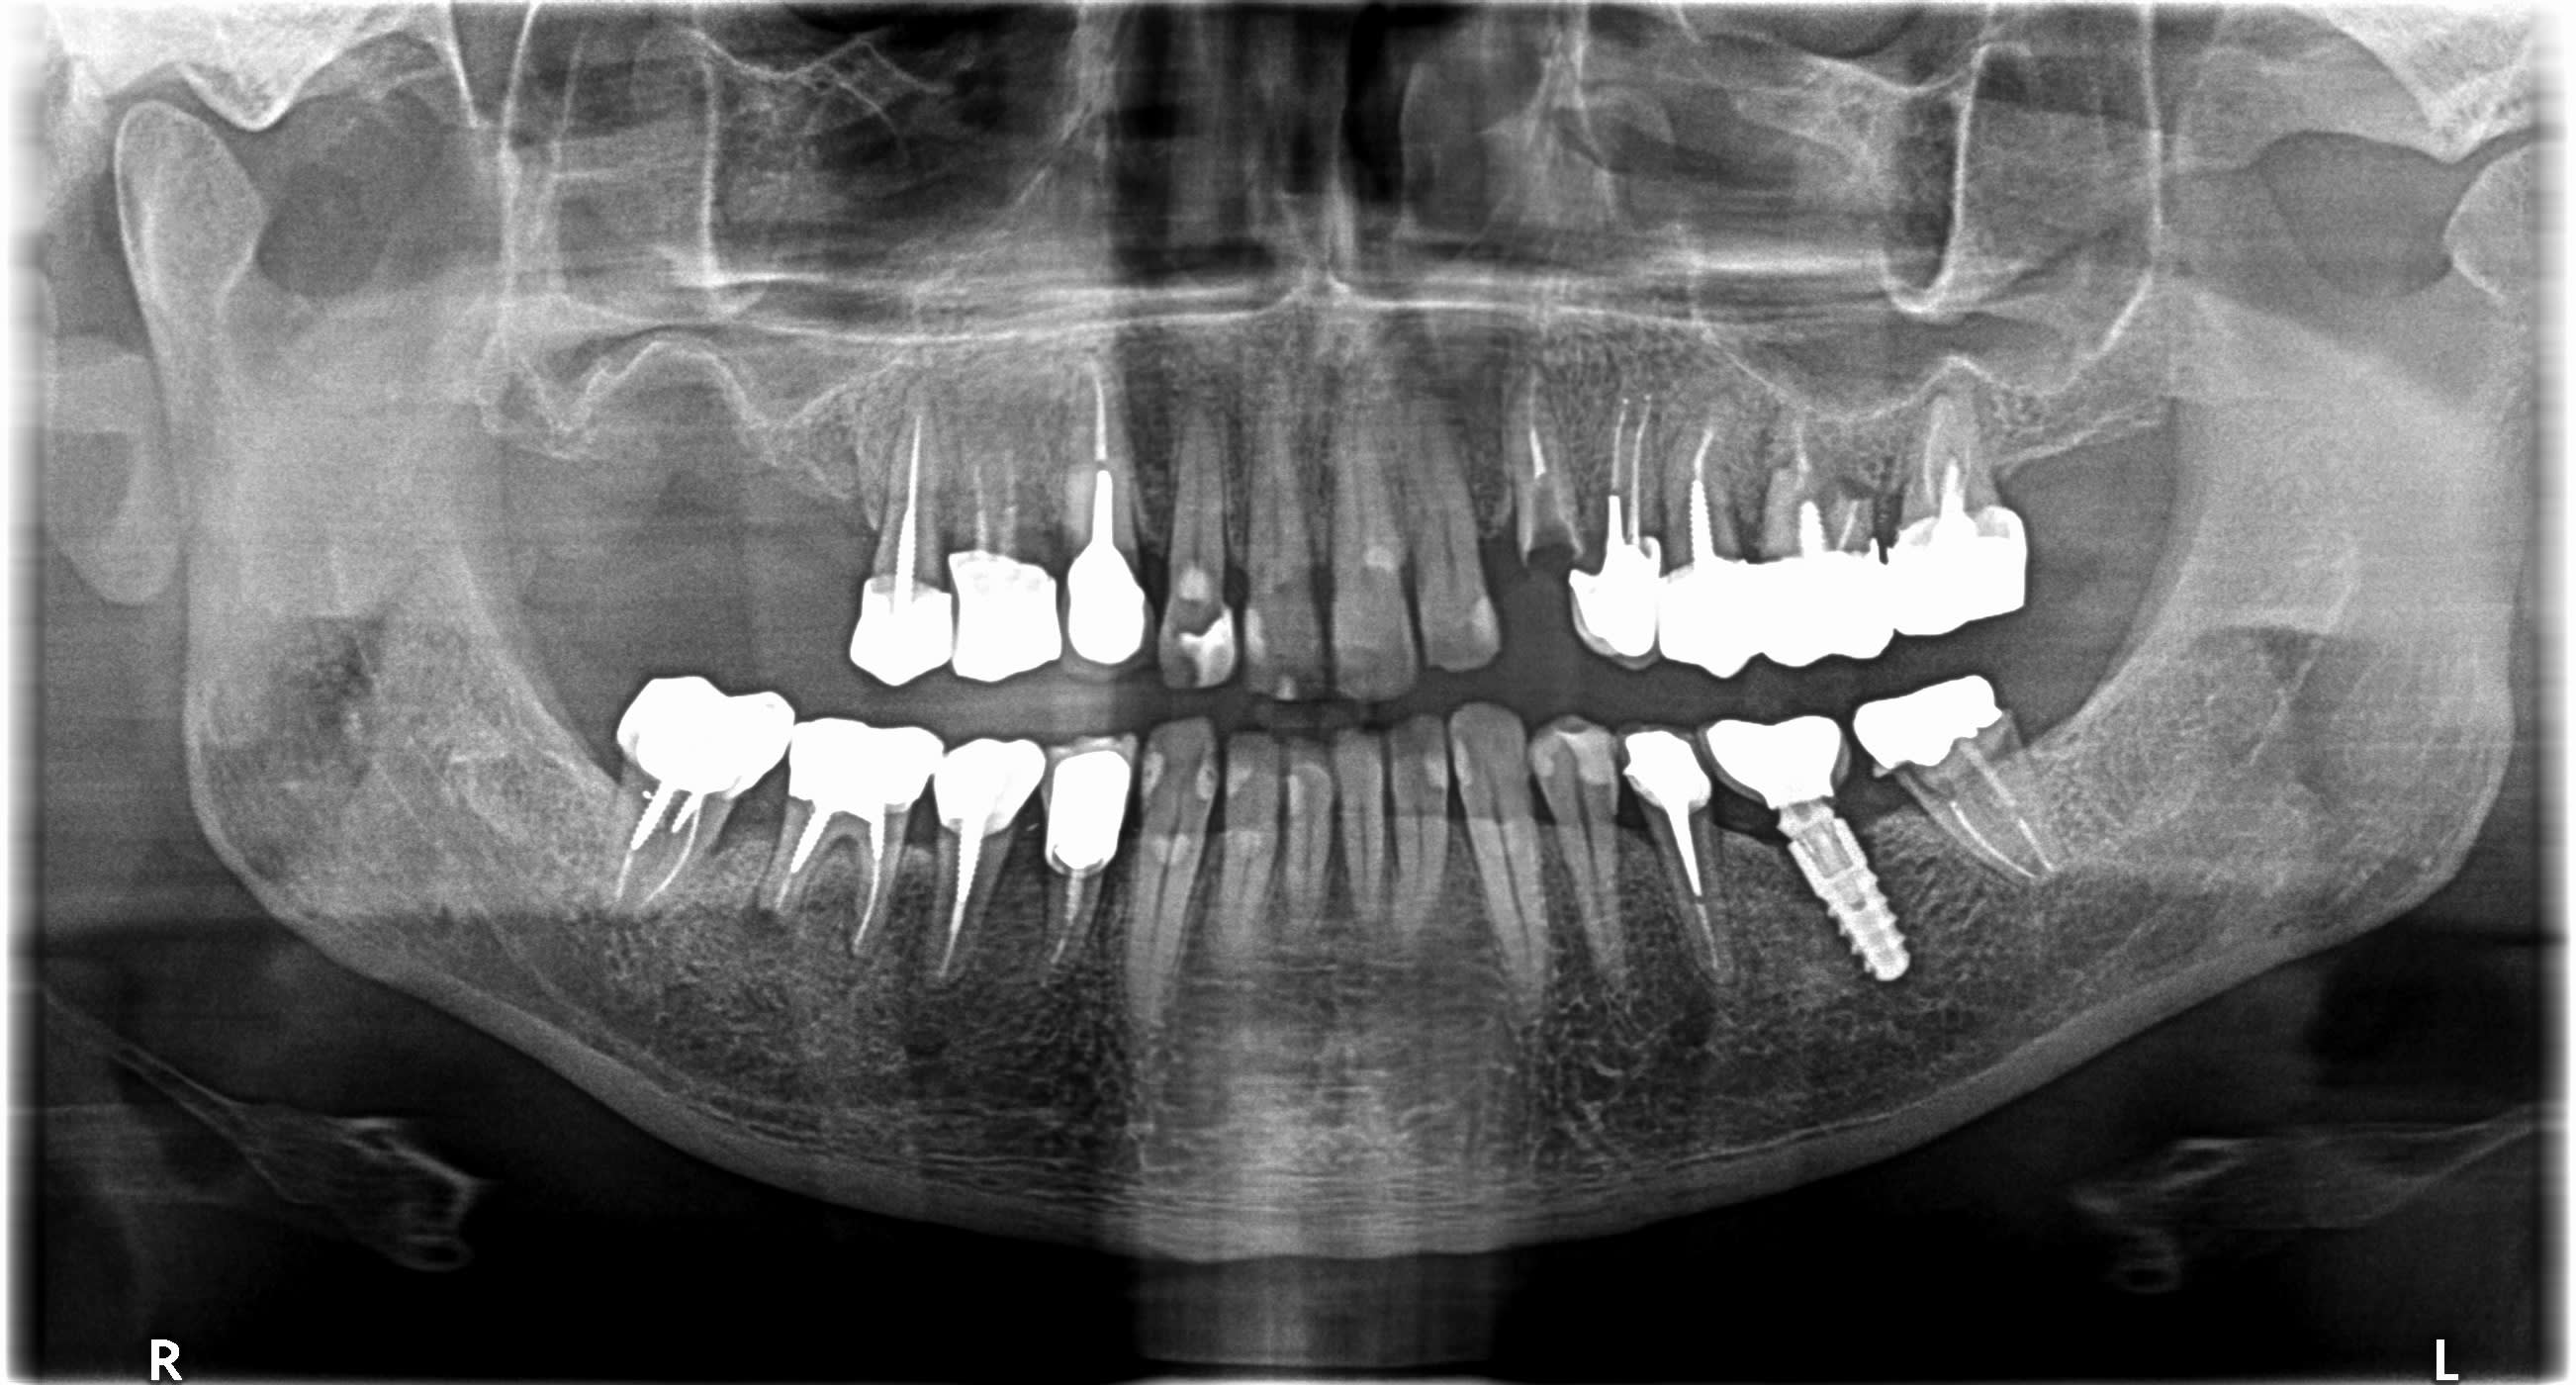

Bonjour, je ne parviens pas à identifier cet implant.

Implant posé par un confrère de St Omer il y a qq années et qui a mis fin à ses jours depuis.

TIOLOGIC DENTAURUM

https://shop.dentaurum.fr/index.php?id=pg&pgsn=3194&ch=dacea3